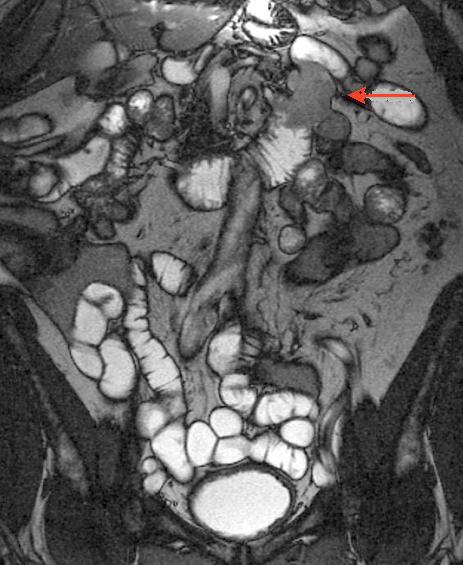

Image IRM de GIST ( fleche

rouge ) |